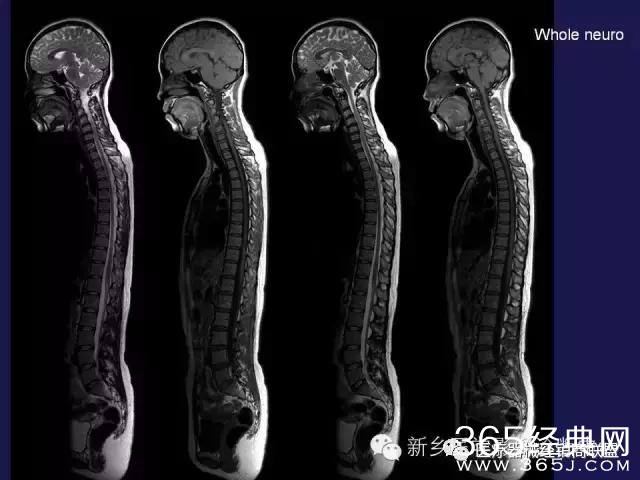

CT、MRI很难?NO,今日我们一起来学习一下如何读CT、MRI!

内行看门道:

整整90张图